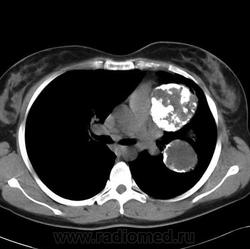

Пациентка Б., 1984 года рождения. С 17 лет наблюдалась с узловыми образованиями в легких (рис. 2, А), по поводу которых в возрасте 25 лет с диагностической целью была выполнена торакотомия слева с краевой резекцией нижней доли левого легкого.

рис.2В. КТ органов грудной клетки в горизонтальной проекции через 7 лет.

рис.2Г. То же, что на рис. В (другой уровень).

При гистологическом исследовании констатирована хондрома легкого. В ходе гастроскопии тогда же выявлена неэпителиальная опухоль желудка. Для уточнения диагноза и тактики лечения больная была направлена в РОНЦ им. Н.Н.Блохина. При повторной гастроскопии в антральном отделе с переходом на нижнюю треть тела желудка по передней стенке и малой кривизне определялось многоузловое подслизистое образование протяженностью около 7 см, с поверхностными изъязвлениями; аналогичное образование диаметром около 3 см выявлялось в средней трети тела желудка по малой кривизне. При гистологическом исследовании биоптата определялись крупноочаговые разрастания опухоли из веретенообразных и эпителиоидных клеток, принадлежащих ГИСО. В ходе УЗИ органов брюшной полости выявлены множественные парагастральные лимфатические узлы до 3,1 х 4,8 см. При рентгенологическом исследовании органов грудной полости (рис. 2,В-Д) отмечена выраженная отрицательная динамика в виде увеличения размеров ранее имевшихся образований в легких и появление новых очагов и фокусов уплотнения. Узлы представляли собой округлые образования с бугристой поверхностью, четкими контурами, неоднородной структуры за счёт обызвестлений, размерами от 0,5 см до 6,1 х 6,6 см, располагавшиеся в обоих легких, преимущественно в левом.